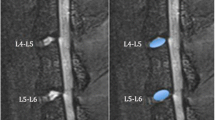

Group-averaged enhancement maps in the CEPs and SBs are shown in Fig. 7. Each column shows enhancement maps grouped by the degeneration grade of the adjacent disc. SB enhancement maps are overlaid onto the template vertebral body and enhancement in cranial and caudal CEPs were shown as two separate surfaces between the two vertebral bodies (NP removed). There were 190 healthy (grades I and II), 51 grade III, 33 grade IV and 6 grade V discs. Different scales had to be used for color maps in CEPs and adjacent SBs in this graph because of the large difference in enhancement peaks between those two regions.

Voxelwise enhancement maps in CEP and SB ROIs projected and transformed onto the template as described in Fig. 4. Enhancement maps were grouped according to the degeneration grade of the corresponding disc and averaged to generate these maps. Color bars are included next to the plots to describe colors used in these maps. Different scales were used for CEP and SB regions. Also note that CEP and SB regions around Grade V discs had substantially elevated enhancement, therefore the scales had to be almost doubled to capture the increased dynamic range

Another interesting finding in our study was the difference between cranial and caudal CEPs. Average enhancement in cranial CEPs was significantly different between discs with different grades (p = 0.0161), whereas a similar trend was seen in the caudal CEPs, but it was not statistically significant (p = 0.066). This effect can also be seen clearly in the spatial enhancement maps of Fig. 7. There is a visible increase in enhancement in the cranial CEPs while it is less pronounced in the caudal CEPs. This might be partly due to the fact that average enhancement was consistently lower in the caudal CEPs (Fig. 5) across all degeneration grades and the rate of increase also appears to be lower. The reason for this discrepancy is not clear and we could not find any evidence from the literature to explain it. Further studies are needed to understand this difference. However, it is worth noting that if we analyze only the enhancements in the peripheral regions of the CEPs, both of the cranial and caudal sides show significant association with degeneration. Another striking finding was the opposite differential enhancements in SBs. Both average enhancement plots (Fig. 5) and spatial enhancement maps (Fig. 7) show that caudal SBs have higher enhancement than the cranial ones. This observation is in accord with earlier cadaver studies in which they demonstrated that the caudal SBs are thinner and more prone to fractures [26, 27], which might lead to increased leakage of contrast agent. However, it is not clear why the differential enhancement in caudal versus cranial SBs is the opposite of what is seen in CEPs. Differences in endplate permeability or endplate calcification might play a role in the results seen here. Additional studies are needed to understand these trends.

Figures 6 and 7 also show that the central CEP regions had higher enhancement than the periphery in healthy discs. This is expected since the density of the capillary bed is higher near the NP. However, this typical distribution in healthy SBs and CEPs changed as the discs degenerated. In the extreme case of Grade V discs, the distribution became highly irregular.